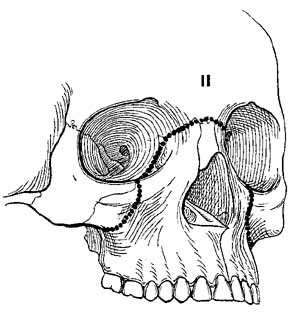

Complex orbital fractures include LeFort, naso–orbital–ethmoidal, zygomatic–maxillary–complex (ZMC or trimalar) and rim fractures. Generally, these fractures are repaired with a multidisciplinary approach provided by plastic surgeons, otolaryngologists, or maxillofacial surgeons. Fractures of the zygoma usually produce a ZMC fracture at three articulation sites: the frontozygomatic suture, the zygomaticotemporal suture, and the zygomaticomaxillary suture. The fracture may cause palpable step-offs of the orbital rim, flattening of the malar eminence, inferior displacement of the lateral canthus, and enophthalmos. The LeFort I (Guerin's) fracture occurs horizontally across the maxilla at the base of the nasal septum, is caused by trauma to the lower midface, results in malocclusion, and does not involve the orbit. The LeFort II (pyramidal) fracture extends from the nasofrontal suture along the nasal bridge to the medial wall at the level of the cribriform plate, posteriorly onto the orbital floor, and through the maxillary sinus (Fig. 14). This fracture results from trauma to the anterior mid-face, which causes a disarticulation of the body of the maxilla and mid-face from the zygomatic arch and cranium. In these injuries, the mid-face often has a sunk-in appearance.61 Epistaxis is a common associated finding. The more ominous cerebrospinal fluid rhinorrhea also occurs frequently, and it requires consultation of a neurosurgeon. A palpable inferior orbital rim step-off may be associated with infraorbital hypesthesia. Optic nerve trauma must be suspected. The globe may be enophthalmic and vertically displaced, and it may demonstrate extraocular motility disturbances.

Fig. 14 LeFort II fracture. (From Iliff NT: The ophthalmic implications of the correction of late enophthalmos following severe midfacial trauma. Trans Am Ophthalmol Soc 89:477–548, 1991)